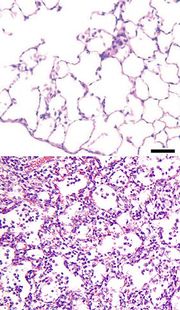

Zápal plic (pneumonie) je zánětlivé onemocnění plic. Obvykle je popisováno jako plicní parenchymální nebo alveolární zánět[1] doprovázený abnormálním plněním plic alveolární tekutinou (alveoly neboli plicní sklípky jsou mikroskopické vzduchem vyplněné váčky uvnitř plic, ve kterých probíhá výměna plynů mezi atmosférou a tělem).

Zápal plic může vzniknout z mnoha různých příčin – na podkladě infekce bakteriemi, viry, plísněmi, parazity nejčastěji šířením přenosem pomocí kapénkové infekce, nebo také jako následek chemického či fyzikálního poškození plicního parenchymu například vdechováním tuhých částic, či žaludečního obsahu.[2][3] Zápal plic může být také původu tzv. „idiopatického“ – bez známé příčiny.